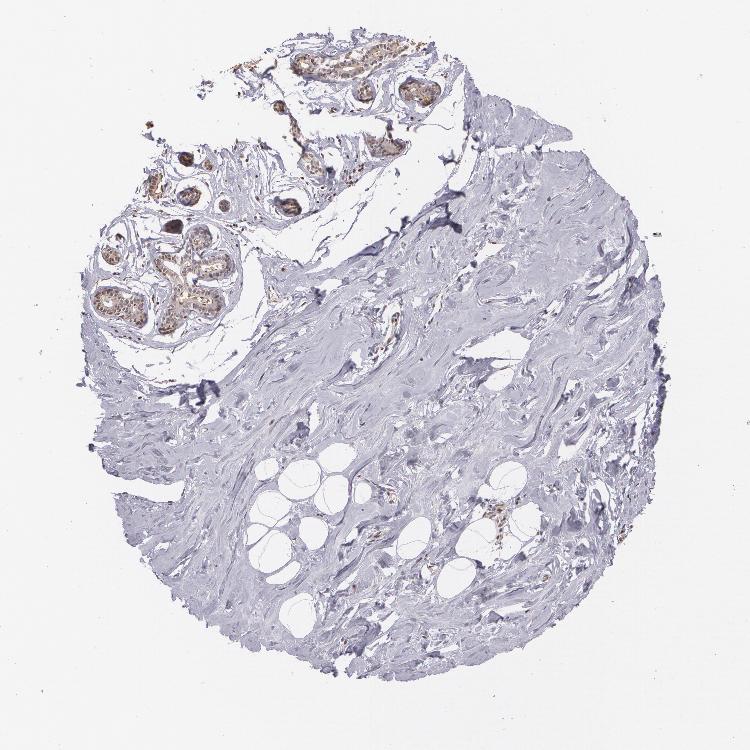

BREAST - Antibody stainingi

Antibody staining in the annotated cell types in the current human tissue is reported as not detected, low, medium, or high, based on conventional immunohistochemistry profiling in selected tissues. This score is based on the combination of the staining intensity and fraction of stained cells.

Each image is clickable and will lead to virtual microscopy that enables deeper exploration of all samples and also displays staining intensity scores, fraction scores and subcellular localization as well as patient and tissue information for each sample.

Antibody HPA004179Antibody HPA007235Antibody HPA008855Antibody CAB000036Antibody CAB001986Antibody CAB080102Antibody CAB080103

Adipocytes Not detectedNot detectedNot detectedNot detectedNot detectedNot detected-

Glandular cells MediumLowHighMediumMediumNot detectedMedium

Myoepithelial cells LowNot detectedHighNot detectedNot detectedNot detectedNot detected